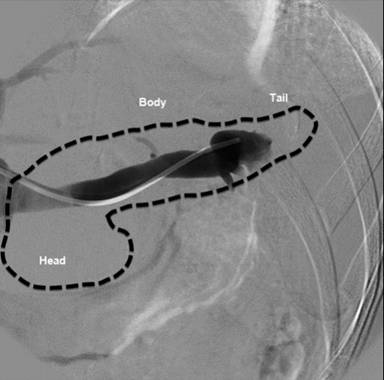

The patient then underwent pancreatic arteriography and splenoportography in order to analyze the amylase concentrations of the head, body and tail of the pancreas (Figure 1). No differences were found between the amylase and lipase concentrations in the three different collection points (splenic hilum, head and body of the pancreas). The results are shown in Table 3. She has been followed up for more than two years with no symptoms at all.

Figure 1. Splenic vein venography. A catheter is placed inside the splenic vein after transhepatic portal vein catheterization. Blood samples are obtained in the three sections of the pancreas (tail, body, and head). |